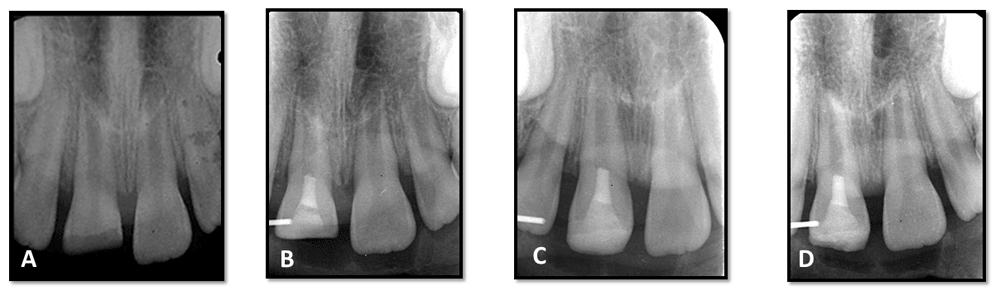

An 8.5-year-old Egyptian girl came to the outpatient clinic of Pediatric Dentistry and Dental Public Health Department, Faculty of Dentistry, Cairo University with the chief complaint of fractured upper right central incisor due to trauma one and half months previously (Figure 1A and B). The patient’s medical history was non-contributory. On clinical examination (which included a visual examination for any abnormalities, palpation of labial vestibule, percussion test and sensibility test), the tooth was sensitive to percussion, which was determined by tapping the tooth with the back of the mirror. The surrounding soft tissue had no tenderness to finger palpation and the tooth had no response to the hot test in comparison to the contralateral tooth. Preoperative radiographic examination revealed a wide root canal with an open apex (Figure 2A) using conventional periapical radiograph.

A) preoperative periapical radiograph; B) immediate postoperative radiograph after mineral trioxide aggregate coronal plug application; C) follow up radiograph at six months; and D) follow-up radiograph at 12 months.

Aseptim solution (SciCan Ltd, Denfotex Light Systems Ltd, Inverkeithing, Scotland) was applied to the canal, followed by a low power laser diode red light system (Aseptim system, SciCan Ltd, Denfotex Light Systems Ltd, Inverkeithing, Scotland) with a specific wavelength (635nm) to activate the aseptim solution for 150 seconds. Canals was washed with saline to remove the aseptim solution. Gentle, copious, irrigation with 20ml of 17% EDTA was applied. Dryness with paper points to remove excess EDTA was done. Bleeding was initiated into the canal system by rotating a K-file at 2mm beyond the apical foramen. A resorbable matrix (Collacote dressing Zimmer Biomet, USA) was placed over the blood clot. Then, white mineral trioxide aggregate (MTA) (Angelus, Brazil) was placed over the matrix with placement of a moistened pellet of cotton and glass ionomer (Figure 2B). After two days, the tooth was double sealed using glass ionomer cement (Kromoglass 2, LASCOD- Italy) and composite restoration 3M composite (3M, America Inc).

Clinical examination of the patient revealed no adverse signs and symptoms at three, six-, nine- and 12-month follow-up periods (Figure 1C and 1D). Radiographic examination revealed an increase in root length and root thickness at six months (Figure 2C) and complete root closure at 12 months (Figure 2D) using digital radiography (Digora™ Optime UV) and digital software (Soredex, Finland). (Table 1)